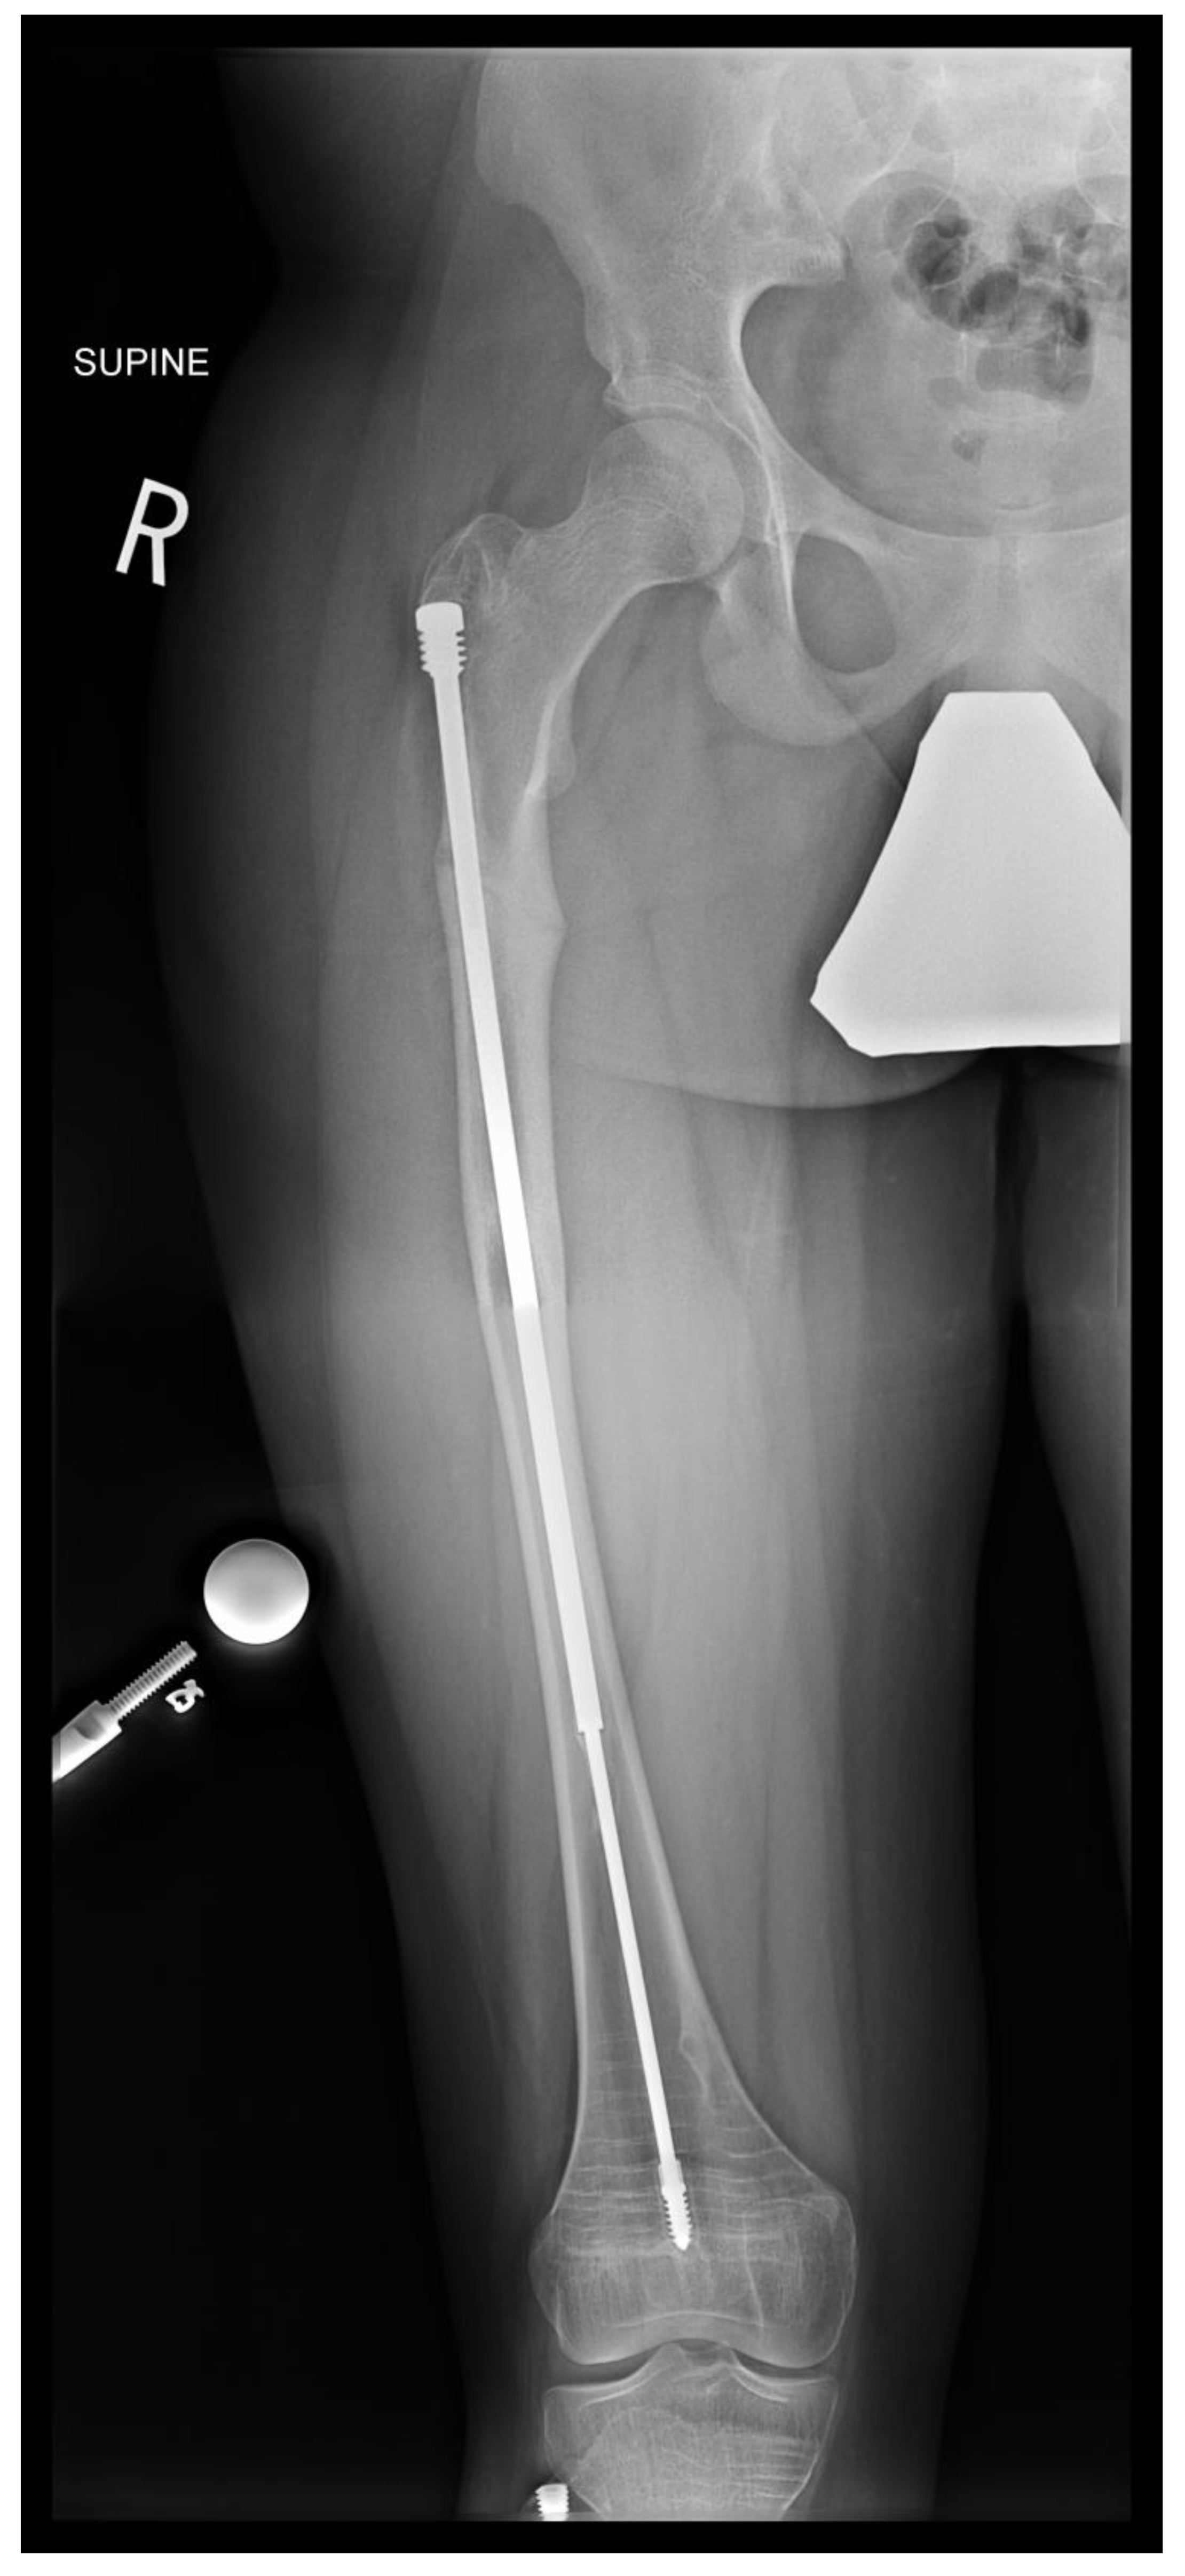

Figure 10. A - Pre-operative X-ray. B- Post-revision X-ray showing installed SLIM nail in the left femur.

In the second case presented in this paper, a 15-year-old boy diagnosed with OI type IV, who was previously operated on 12 years ago with bilateral FD rods, presented to his regular clinic visit with pain over the left greater trochanter. This patient was ambulating without any braces or aids and was functioning very well. He did not sustain any fractures since the FD rod insertion, and full ROM of his hips was maintained. X-ray showed a completely disengaged FD rod on the left side, where the female component migrated distally and laterally across the lateral cortex. The protruding proximal part of the female component was the site of the pain and tenderness (Figure 10A). On the right side, the FD rod was almost disengaged, and a mild deformity was present anterolaterally. The X-ray demonstrates that the intramedullary canal is too narrow to accommodate an adult-sized nail. As the patient had almost reached skeletal maturity, it was decided not to use another telescoping rod but instead to use a non-telescoping SLIM nail. Because the distal male component of the existing Fassier Duval rod was situated deep into the canal, making its retrieval problematic, it was decided pre-operatively to leave it in situ and insert the new rod beside it. The female component on the left side needed to be removed, and a solid SLIM rod was inserted to protect the bone (Figure 10B). Revision to a non-telescoping rod was considered for the right side as well, however, surveillance was opted for as the patient was approaching skeletal maturity. In this case, the indication for use of the SLIM nail is a near skeletally mature patient, therefore, not requiring a telescoping nail. However, the intramedullary canal was too narrow to accommodate a larger solid nail.